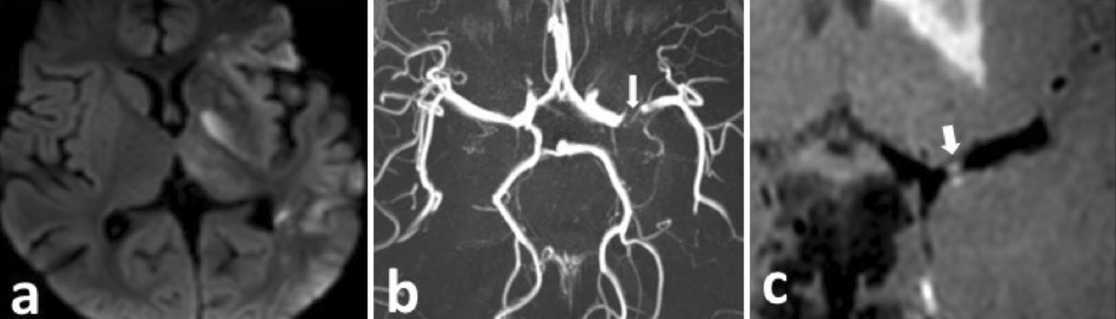

示例一、a、b、c为一例1岁女童,局灶性脑动脉病,表现为右偏瘫,15天前有水痘感染史。a DWI显示左侧MCA区域呈斑片状弥散抑制,提示亚急性脑梗死。b MIP轴向TOF MRA图像显示左侧M1 MCA严重局灶性狭窄(箭头)。c 增强后冠状动脉血管壁MR(VWI)显示左侧M1 MCA局部平滑同心圆增强,伴有严重狭窄(箭头所示):